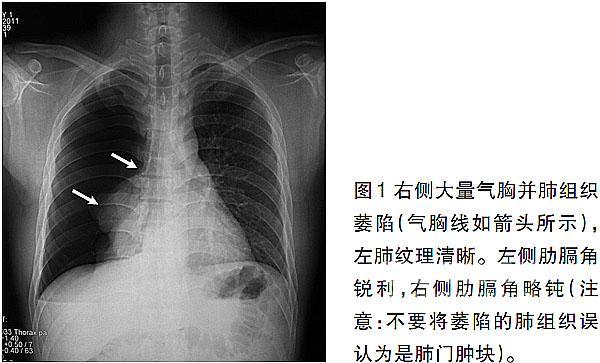

气胸x线胸片图解胸廓,气胸x线胸片图解x光片

气胸患者胸部x线表现

从胸片及ct检查常用于诊断气胸,胸片儿简单便捷.

气胸的x线表现,6个病例帮你搞定